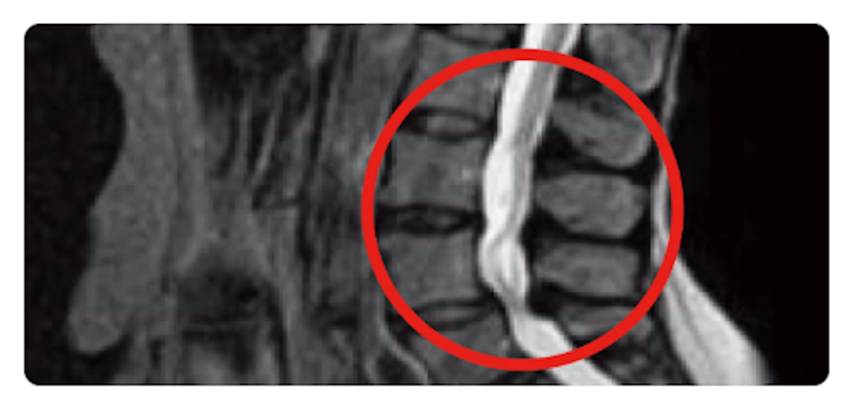

背骨の中にある神経の通り道(=脊柱管)が狭くなった状態は、脊柱管狭窄症といいます。

脊柱管狭窄症とは、神経の通り道である脊柱管が狭窄する(=狭くなる)ことにより、神経が圧迫される状態です。腰椎が不安定なことが原因の場合、身体の動きで痛くなることが多いです。

脊柱管が狭くなると、神経が圧迫されます。神経が圧迫されると、腰の痛みに加えて、下肢の痛みやしびれも発生します。